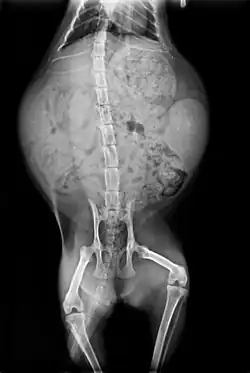

Anatomie des organes vitaux du chat.

Squelette et muscles

L'anatomie du chat est semblable à celle des autres espèces de félidés. Il possède un corps fort et flexible, des réflexes rapides, des dents pointues et des griffes rétractables adaptées à la mise à mort de petites proies.

Le squelette est composé de 250 os. Les vertèbres du cou sont courtes, et la colonne vertébrale est très souple.